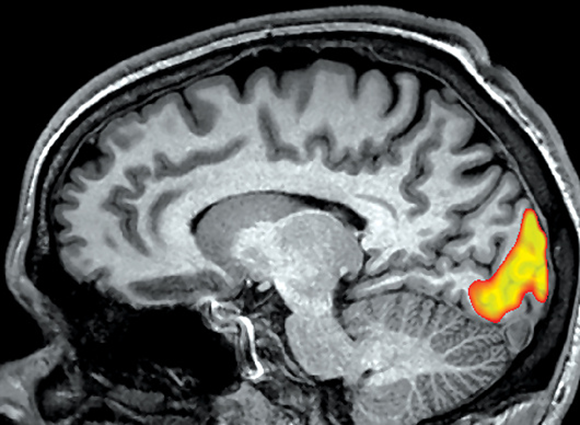

أطلق على الإشارة التي قاسها الباحثون "الإشارة المعتمدة على مستوى أوكسجين الدم". صورة MRI للدماغ، تمّ تمييز عناصر حجمية (ڤوكسل) في منطقة الفصّ القذالي بألوان دافئة، حيث كان هناك تغيير كبير في إشارة BOLD في ظروف التّجربة مقارنةً بوضع الراحة | Living Art Enterprises / Science